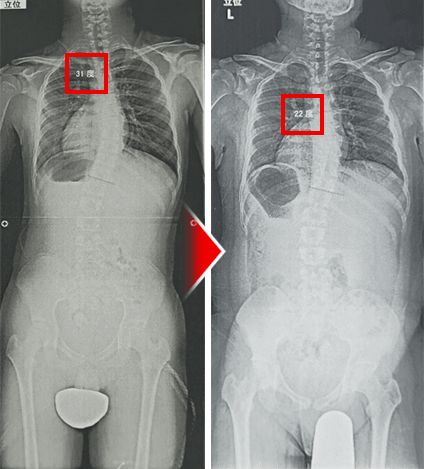

整形外科では一生治らないといわれている側弯症でも、たった1回、10分以内の施術でここまで変化してしまいます。しかも、背骨には刺激を加えない、触れる・撫でるだけの施術で出せた結果です。

医師も驚愕した治療効果。レントゲンでも明らかな変化が見られ、コブ角が31度から22度になり側弯症が治りました。

この治療法を2回受けた後の側弯症の変化です。背骨の変形を直に確かめても、C型の側弯がまっすぐに変化しています。